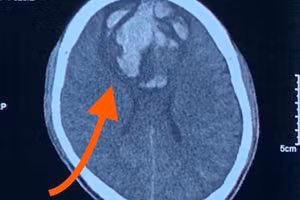

GD&TĐ - Bệnh viện Trung ương Quân đội 108 cảnh báo có nhiều người gặp tai nạn khi lao động để lại nhiều di chứng, trong đó có chấn thương sọ não nặng...